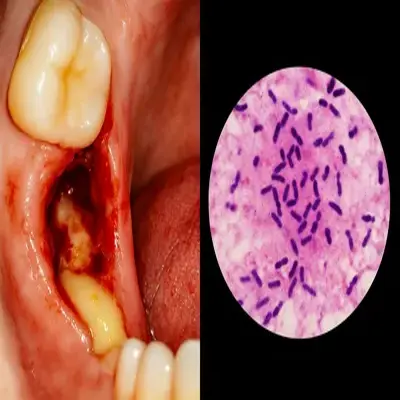

کشیدن دندان عفونتدار زمانی ضرورت پیدا میکند که عفونت ریشه یا بافتهای اطراف به درمانهای حفظی پاسخ نمیدهد و خطر گسترش دارد؛ نشانههایی مثل آبسه دندان تکرارشونده با چرک دندانی، التهاب لثه شدید و ورم فک، درد ضرباندار، حساسیت به ضربه و ضایعه بزرگ پریآپیکال در رادیوگرافی.

حفره دندان ملتهب با ترشح چرک و خونریزی

تفاوت کیست، گرانولوم و آبسه به زبان ساده

گرانولوم دندانی: التهاب کوچک اطراف ریشه که معمولاً بعد از کشیدن یا درمان ریشه برطرف میشود.

آبسه دندانی: تجمع چرک فعال همراه با درد و تورم که نیاز به تخلیه فوری دارد.

کیست دندانی: ضایعهای با دیواره مشخص که ممکن است حتی بعد از کشیدن دندان هم باقی بماند و نیاز به جراحی داشته باشد.